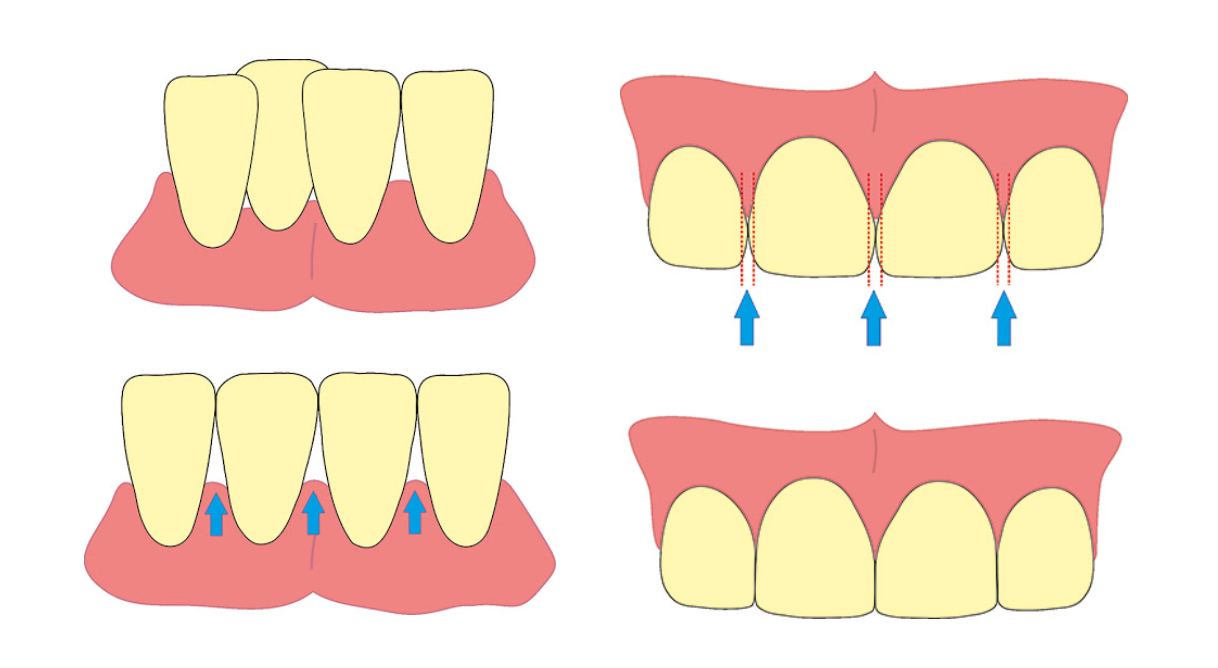

Ces écarts sont le résultat de dents en forme triangulaire ou de perte de pulpe dentaire. Dans ce genre de cas, le stripping peut éliminer le point de contact et donner aux dents une forme plus quadrangulaire dans laquelle les bords deviennent parallèles.

Source : Healthline

Les autres applications de ce remodelage des dents concernent les écarts de taille et de longueur des dents, la correction de l'overjet et les incisives inclinées.

Source : Impress